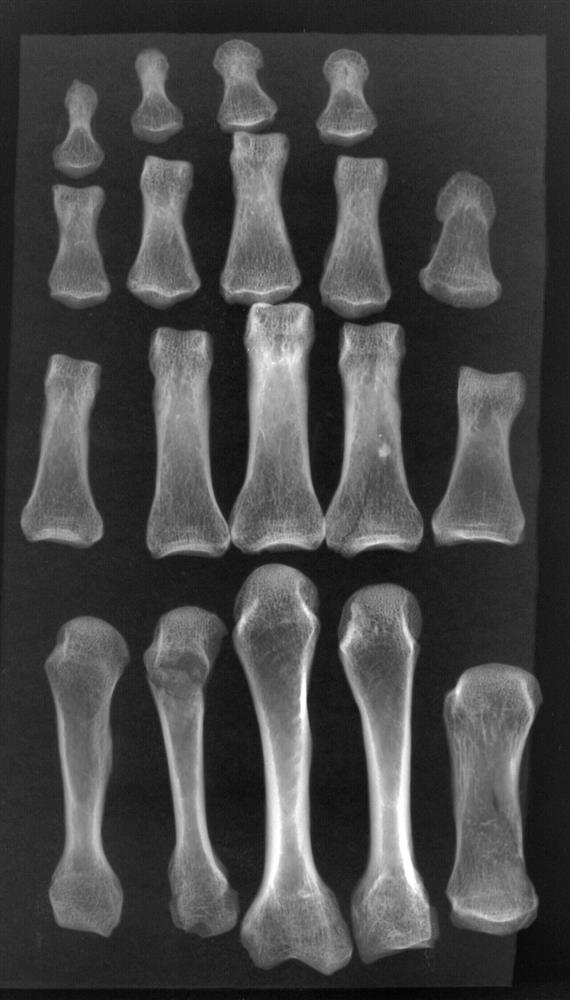

Микрофокусная рентгенограмма костей кисти мужчины Сунгирь 1 со следами функциональной гипертрофии

Компьютерная томография и микрофокусная рентгенография уточнили обстоятельства жизни сунгирца из погребения 1. По степени внутренней массивности костей кисти мужчина с сунгирской стоянки сближается с представителями более архаического человечества – с неандертальцами. Таков был результат рабочей гипертрофии костной ткани под действием физических нагрузок у этого человека – могучего охотника, изготавливавшего и активно использовавшего каменные орудия труда.